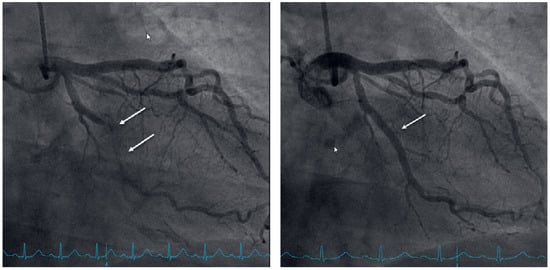

To exclude coronary artery disease the patient was referred for a cardiac single photon emission computed tomography (SPECT) scan using technetium-99m, which revealed a normal radionuclide tissue distribution at rest, but after physical stress using a bicycle ergometer significant left ventricular inferior-lateral ischaemia of 10–15% was observed (Figure 2). Elective coronary angiography confirmed coronary artery disease with chronic total obstruction of the left circumflex artery. One drug-eluting stent was placed successfully (Figure 3).

Figure 2. Single-photon emission computed tomography (SPECT); arrows indicate ischaemia in the area supplied by the left circumflex artery.